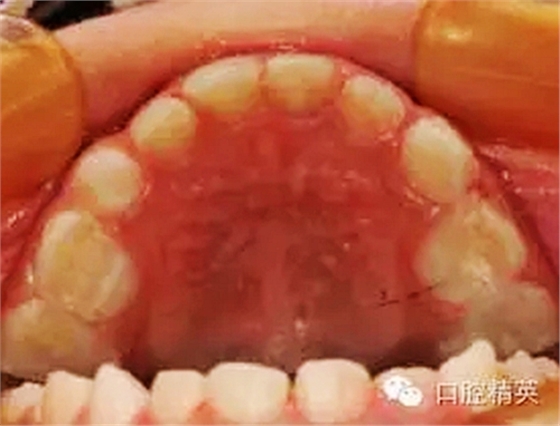

臨床檢查:頜面部及頸部未見明顯異常。口腔衛(wèi)生狀況尚可, 52,61,62,63,73唇舌面齲,54,64,74,84牙合面齲壞,腐質(zhì)中等,叩(-),松(-),牙齦未見明顯異常;75牙合面深齲壞,大量軟腐,叩(-),松(-),牙齦未見明顯異常,腐質(zhì)未去凈見露髓孔;51大面積齲壞,大量腐質(zhì),叩(+),松(Ⅰ),唇側(cè)牙齦可見5mm×6mm的包,軟;余牙未見異常。

①52,61,62,63,73,54,64,74,84去腐備洞,氫氧化鈣墊底,全酸蝕,DE-BOND加3M樹脂充填,調(diào)合,磨光。

②75,51局麻下開髓、拔髓,根管預備,生理鹽水沖洗,Vitapex根充,鋅汀墊底,全酸蝕,DE-BOND加3M樹脂充填,調(diào)合,磨光。